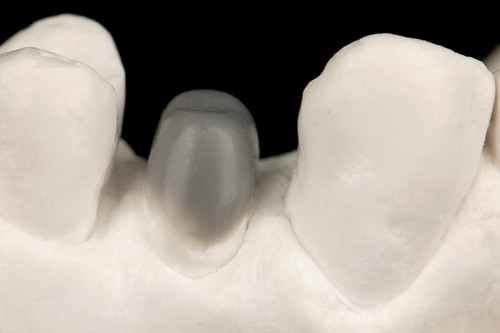

After completion of the endodontic treatment and crown lengthening to develop an ideal ferrule effect (Figure 3 through Figure 5) a diagnostic wax-up was fabricated to an ideal coronal preparation geometric shape, dimension, and height for the anticipated final composite core buildup (Figure 6). A clear polyvinyl siloxane (PVS) impression material was injected into a nonperforated tray, placed over the diagnostic wax-up, and then put into a pressure pot with cold water for 5 minutes. This procedure is aimed at reducing the potential for the formation of voids and bubbles in the impression material (Figure 7 and Figure 8). A small opening was made above the tooth to be restored using a tapered diamond bur (6847) (Figure 9). It is important to clean the internal surfaces with a microbrush to prevent silicone debris from integrating into the flowable material. Prior to the restorative procedure, a diagnostic wax-up was fabricated to the anticipated extracoronal contours for development of the final crown (Figure 10).

Fig 6. A diagnostic wax-up was fabricated to an ideal coronal preparation geometric shape, dimension, and height for the anticipated final composite core buildup.

Figure 6

Fig 10. Prior to the restorative procedure, a diagnostic wax-up was fabricated to the anticipated extracoronal contours for development of the final crown.

Figure 10